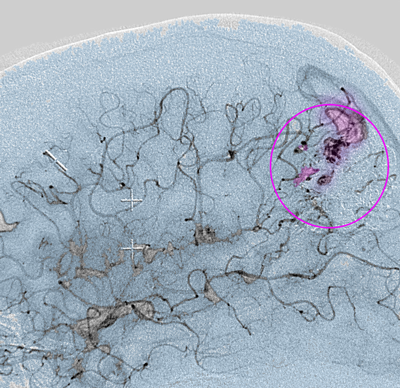

AVM2

Αρτηριοφλεβώδης δυσπλασία (περίγραμμα).

Η θεραπεία των αρτηριοφλεβωδών δυσπλασιών είναι αρκετά σύνθετη και εξαρτάται από το μέγεθος, την θέση τους και τα αγγειακά χαρακτηριστικά τους. Μπορούν να αντιμετωπιστούν με χειρουργική επέμβαση, εμβολισμό, ακτινοχειρουργική γ-knife ή οποιοδήποτε συνδυασμό των ανωτέρω. Σκοπός της θεραπείας είναι να αποκλειστεί η αρτηριοφλεβώδης δυσπλασία από την αγγειακή κυκλοφορία χωρίς να επηρεαστεί η λειτουργία του εγκεφάλου.